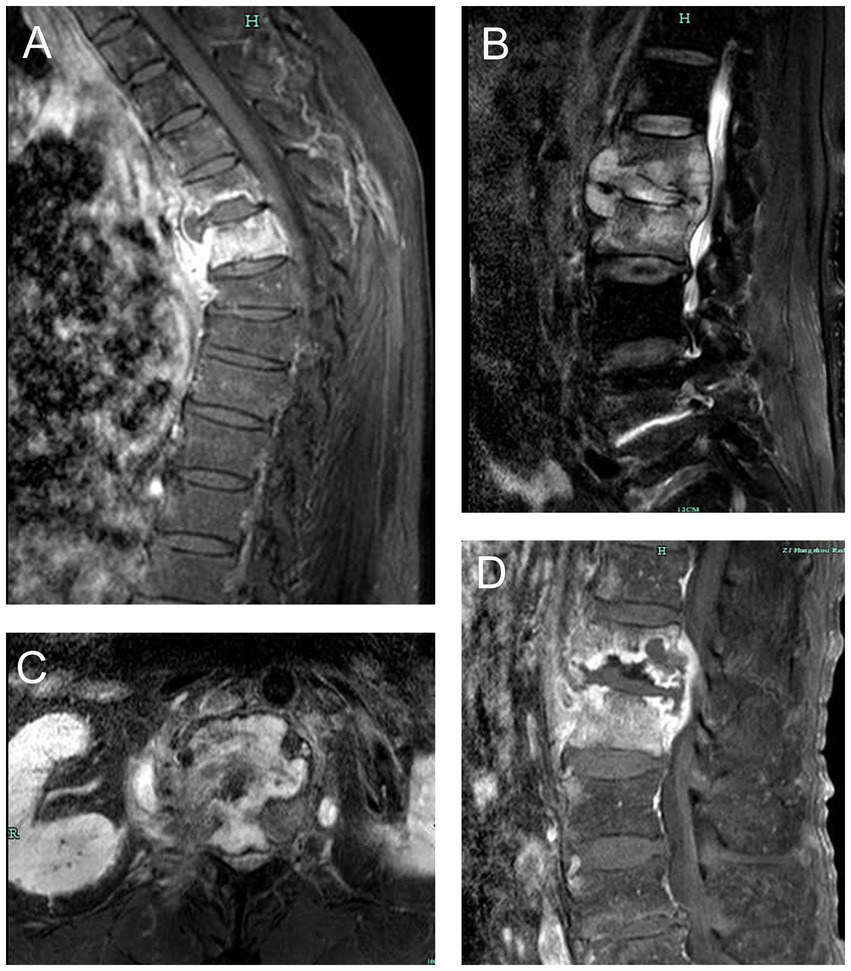

The composite reference standard served as the diagnostic reference standard for this investigation (CRS). The included patients were segregated into two groups based on the CRS. Patients with typical symptoms of TB poisoning, magnetic resonance imaging of the spine suggestive of TB, positive TB immunoassay (interferon-γ release assays), positive AFB smear or culture in spine samples, positive other TB nucleic acid amplification tests (such as Xpert MTB/RIF), combined PTB or other EPTB, effective anti-TB treatment were diagnosed with STB. Magnetic resonance imaging changes of STB was presented in Figure 1. Patients with negative AFB smear and culture, no evidence of TB infection, clear other causes of spinal lesions, and ineffective anti-TB treatment were diagnosed as non-STB.

Figure 1

Magnetic resonance imaging changes of spinal tuberculosis. (A) thoracic tuberculosis leading to destruction of vertebral body and prevertebral abscess. (B) lumbar tuberculosis leading to destruction of vertebral body, intervertebral disk and prevertebral abscess. (C) lumbar tuberculosis leading to destruction of lumbar vertebral body. (D) lumbar tuberculosis leading to worm-bite like destruction of vertebral body and intervertebral disk.